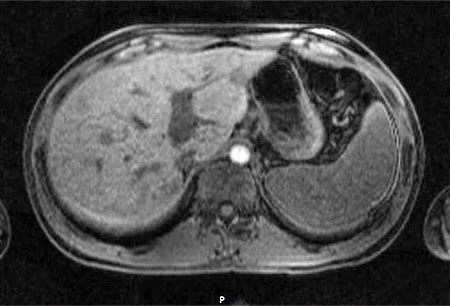

Bartonella infection

MRI abdomen, cat-scratch disease with disseminated infection: multiple small abscesses in liver, micro-abscesses in spleen

From the collection of Janak Koirala, MD